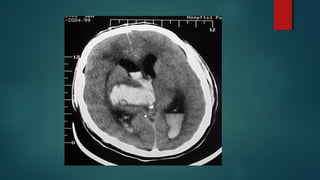

Este documento es el programa para un taller de imágenes del curso de emergencia 2015 impartido por el Dr. Víctor Delgado. El taller se centra en el uso de imágenes médicas para el diagnóstico y tratamiento de pacientes en coma traumático según la base de datos de Marshall. El Dr. Delgado es el único instructor repetido a lo largo del documento.